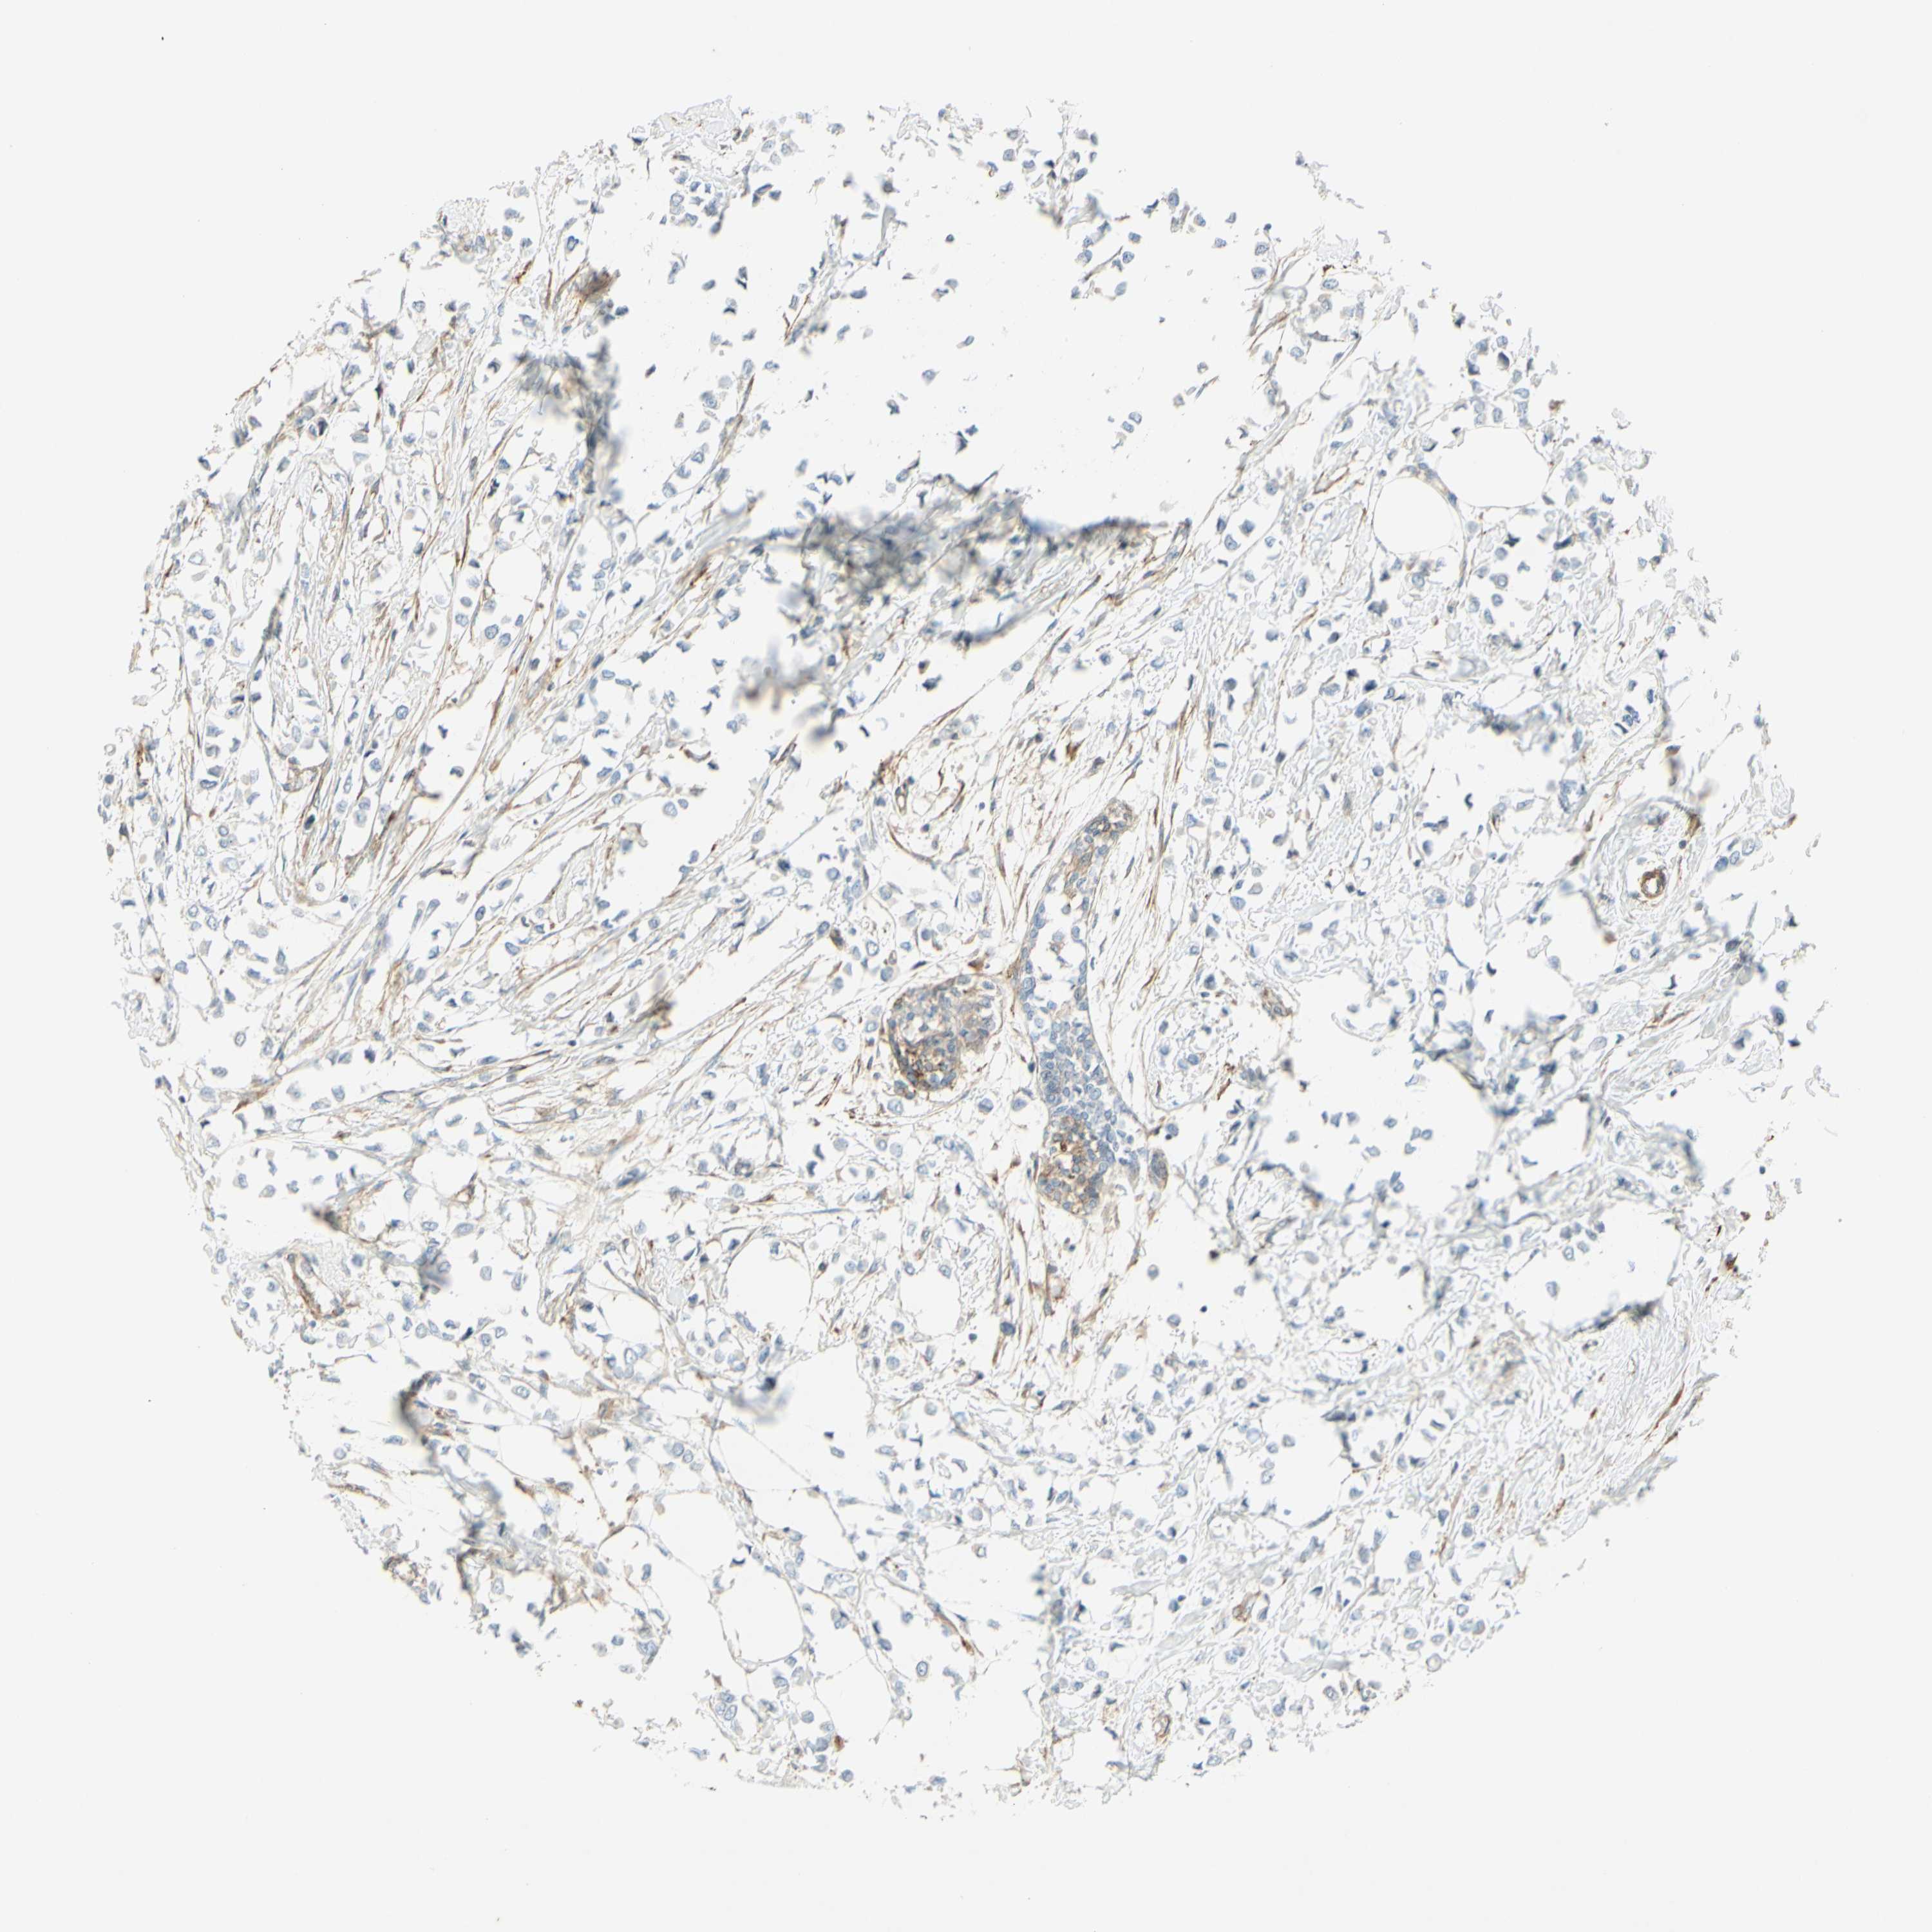

CANCER BREAST CANCER Show tissue menu

BRCA TCGA BRCA VALIDATION PROTEIN EXPRESSION

ANTIBODIES

AND

VALIDATION